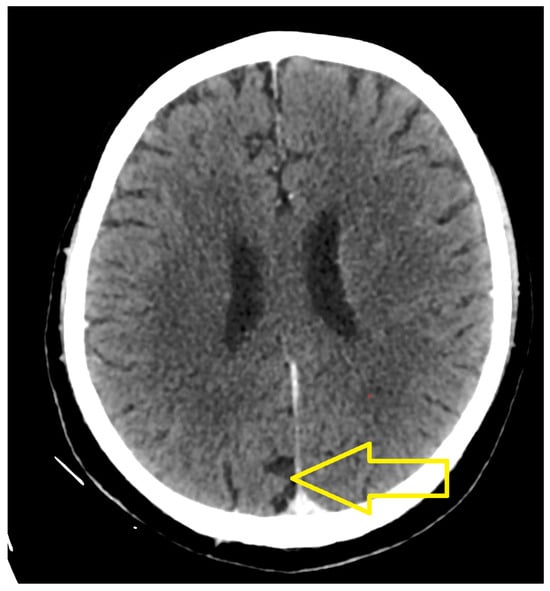

2. Case Presentation